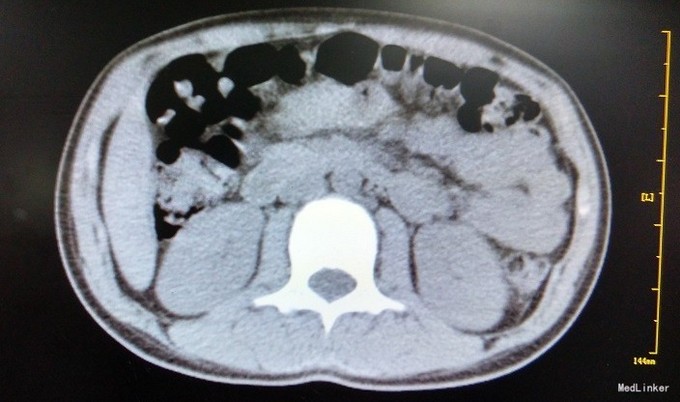

主诉:女,10岁,确诊“1.左侧卵巢无性细胞瘤(Ⅳ期)2.右侧卵巢混合型生殖细胞瘤(无性细胞瘤,绒癌,畸胎瘤)(Ⅳ期)”2+月,拟化疗 病史:患儿于2+月前“因撞击后间断腹痛27天”就诊于当地医院,腹部B超示:盆腔查见大小约7.3*5.4*5.2cm类圆形中等回声团,另于右腹部查见大小约11.6*14.0*12.6cm类圆形中等回声团。1+月前来我院查肿瘤标志物:AFP19.6ng/ml,ThCG33076mIU/ml, CA125:235 U/ml。于我院小儿外科行手术,术后病检为:左侧卵巢无性细胞瘤,右侧卵巢混合型生殖细胞瘤(无性细胞瘤约70%,绒癌约20%,畸胎瘤约10%),术后在我科规律化疗,予以依托泊苷+顺铂+平阳霉素+环磷酰胺化疗,过程顺利,为继续化疗遂入院治疗。

查体:慢性病容,面色及口唇苍白,口腔黏膜略苍白,右侧腹可见约10cm陈旧性手术疤痕。 辅检:血常规:WBC 1.7×109/L 、N:1.01×109/L,Hb75g/L,PLT30*10^9/L,